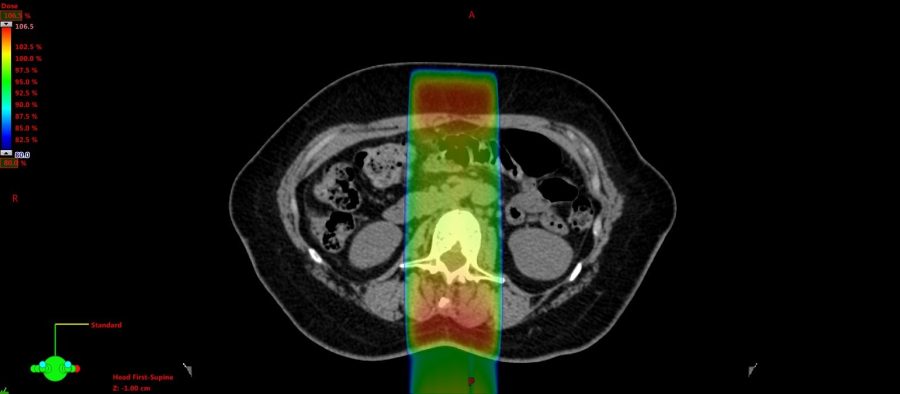

この画像も先ほどと同じ通常照射(左)とIMRT(右)で比較したものです。

原発巣(おおもとの癌)は退治したのですが、時間を空けて脊椎に転移が1ヶ所だけ出てきたパターンです。実は分類的には定位照射というジャンルなのですが、技術的にはIMRTと同様の方法で行われています。

IMRTの方は線量分布の真ん中がポッカリと開いているのが見えますか?ここは脊髄という部分で、放射線が当たりすぎて障害が起きると下半身麻痺などが起きてしまう部分なのです。我々としては何がなんでも障害を出したくない部分です。従来の通常照射ではここを避けることは不可能でした。そのため、脊椎病変への照射はほどほどの線量に抑えることが主流でしたが、そうなると病変を制御できないことも多くありました。IMRTの技術を使うことで前立腺癌同様にリスク臓器の線量を抑えつつ、投与線量を増加させ、病変制御率を向上させることができるようになりました。